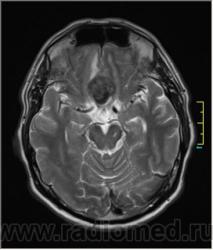

Ax T2:

Ax T2 Flair:

частично функционирующая аневризма

Иначе говоря, аневризма с хронической геморрагией, т.к. мы видим фракции крови различного возраста.

Постепенное пристеночное образование тромбов приводит к появлению типичного для аневризмы феномена -слоистости МР сигнала в полости аневризмы. Данная картина демонстрирует слоистый характер тромботических масс в полости аневризмы .Функционрирующая часть имеет низкий сигнал во всех режимах сканирования. Дополнительно-перифокальный отек.